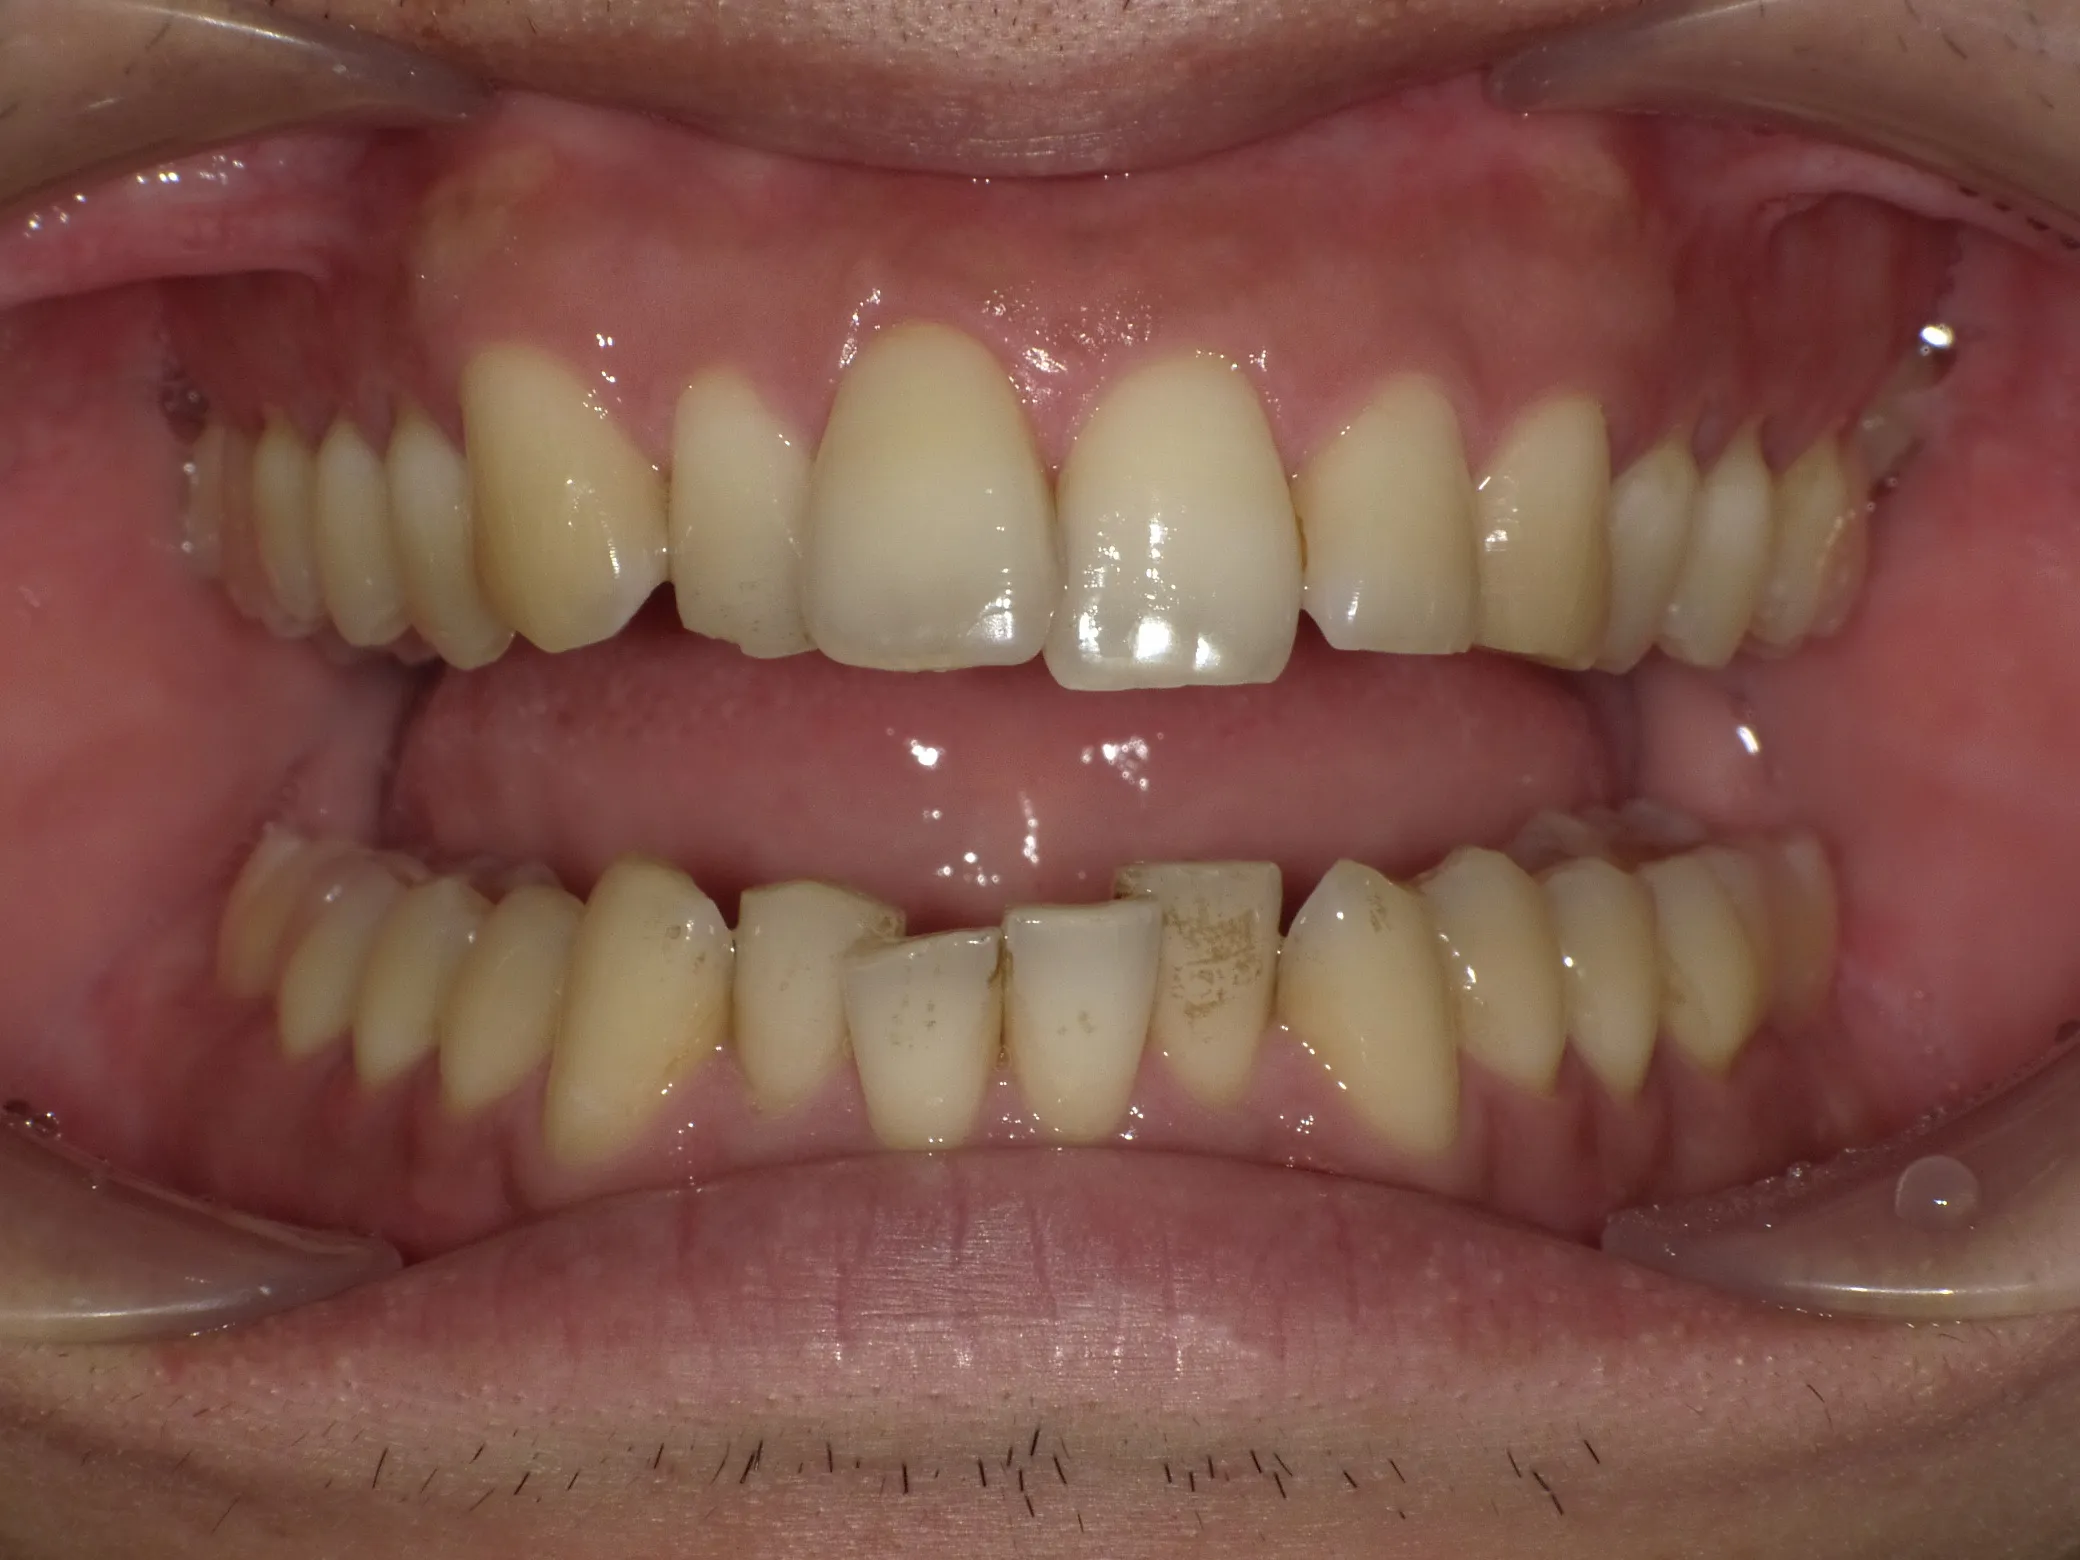

症例②

症例2_治療前 症例2_治療後

年齢・性別 31才・男性

治療方法 ブラケット矯正

治療期間 3年

治療総額 850,000円

特記事項 抜歯あり(4本抜歯)